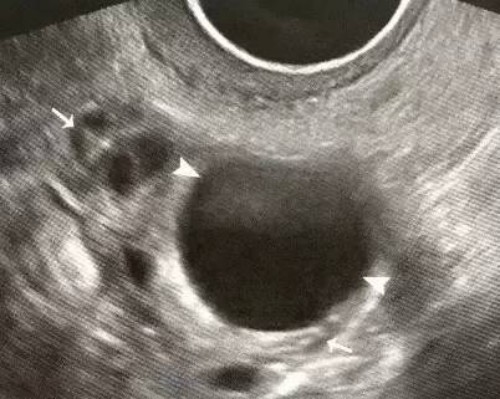

通常情况下,医生会在孩子出生后进行各种检查来确定是否存在18号染色体偏多。最常用的方法之一是进行羊水穿刺或绒毛膜取样。这些过程可以从胎儿中提取细胞,并进行分析以确定其遗传信息是否正常。